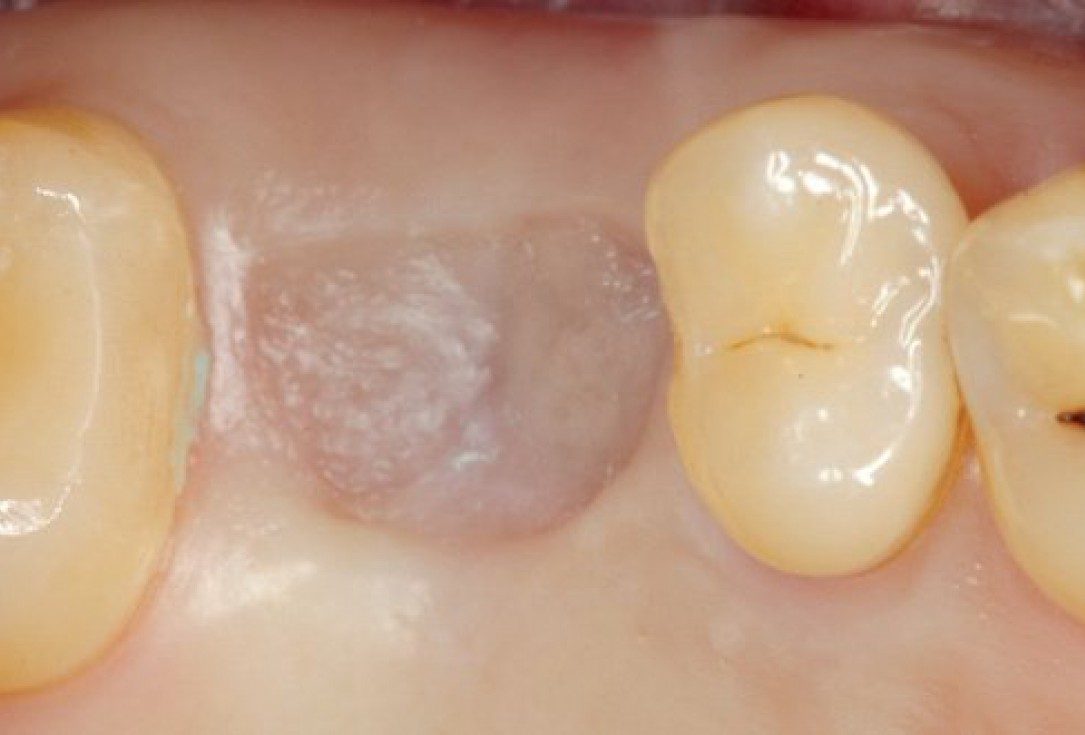

03/10 - Presentation of the soft tissue situation before implantationInternal sinus lift with maxresorb® inject - case Dr. Frank Kistler

01/10 - Endodontically treated tooth 26 with apical cyst formationInternal sinus lift with maxresorb® inject - case Dr. Frank Kistler

Endodontically treated tooth 26 with apical cyst formation